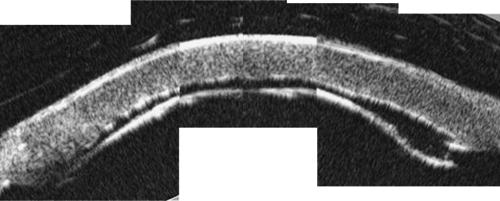

Post-DALK on day 1, examination revealed apposition of the Descemet membrane in the superior half of the cornea and ballooning of the Descemet membrane in the inferior half of the cornea.